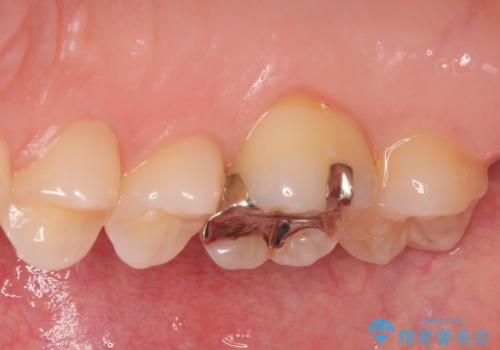

- 銀歯をやり替えたいとのことで来院された患者様です。金属の詰め物の大きさ、虫歯の範囲を考慮してセラミックの詰め物(セラミックインレー)で治療を行っていくことにしました。

拡大鏡視野下で、金属の詰め物(メタルインレー)、虫歯の除去を行い、セラミックインレーに適した形に整えました。

歯と歯茎の間に圧排糸と言われる糸を入れてシリコーン印象材にて精密な型どりをしました。